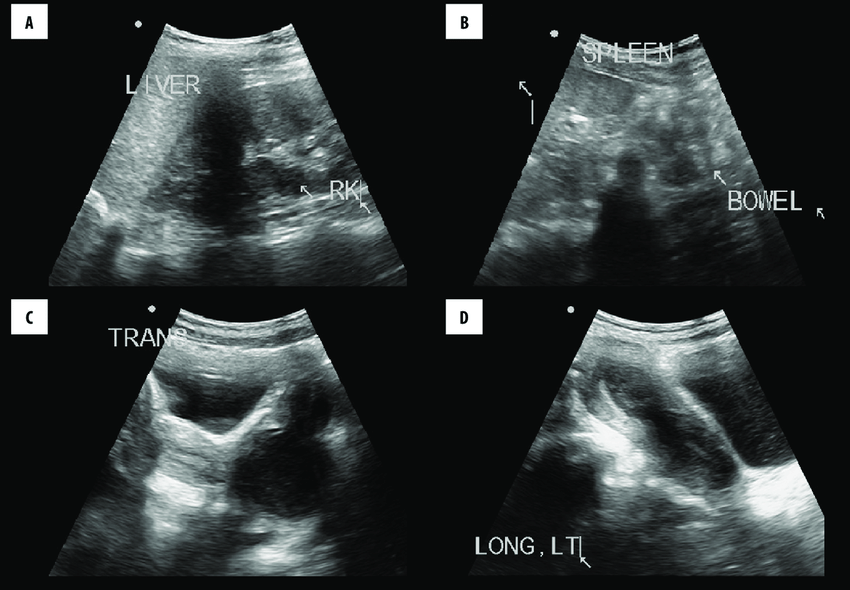

TELE USG REPORTING SOFTWARE

KALPAK has developed web based , internet based reporting software for radiologist to report USG of Abdomen and Pelvis from anywhere in the world. The images and the videos are uploaded to the portal , and the reporting doctor accesses these images and videos for examination and based on the findings by the doctor a detailed USG Abdomen and Pelvis report is generated. The report informs you about the present conditions of various organs like liver, gall bladder, pancreas, left kidney, right kidney, spleen, aorta, IVC, Urinary bladder, uterus, right ovary, left ovary, intestines , EO fluid etc which is based on the images and videos of the of the abdomen and pelvic region..